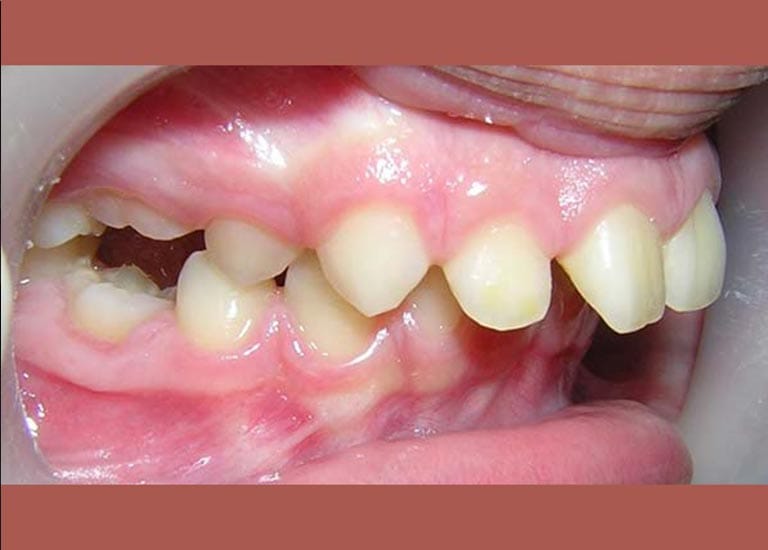

BEFORE

A case of severe protrusion in the upper anterior teeth that we treated with Mandibular Anterior Repositioning Appliance at first stage -which is is used to move the lower jaw forward- and then completed the treatment using a conventional orthodontic device.